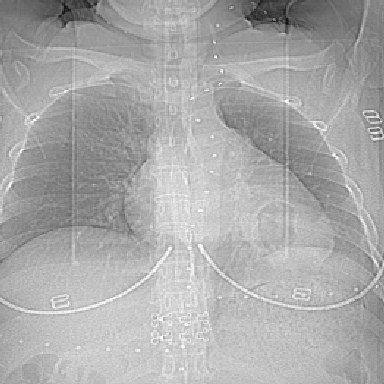

f 37 咳嗽1周,咯血1次,无浓痰,无明显发热

左下肺肿块影,内可以见小泡征,并见厚壁空洞形成,洞内缘凹凸不平,可见壁结节。靠近胸膜侧可见胸膜凹陷征。左侧胸腔内可见少量低密度积液影。右肺可见两处高致密的小结节影。

考虑:左下肺周围型肺癌伴右肺转移

左下肺肿块影,内可以见小泡征,并见厚壁空洞形成,洞内缘凹凸不平,可见壁结节。靠近胸膜侧可见胸膜凹陷征。左侧胸腔内可见少量低密度积液影。双肺可见多发性小结节影。

考虑:左下肺癌性空洞伴两肺转移